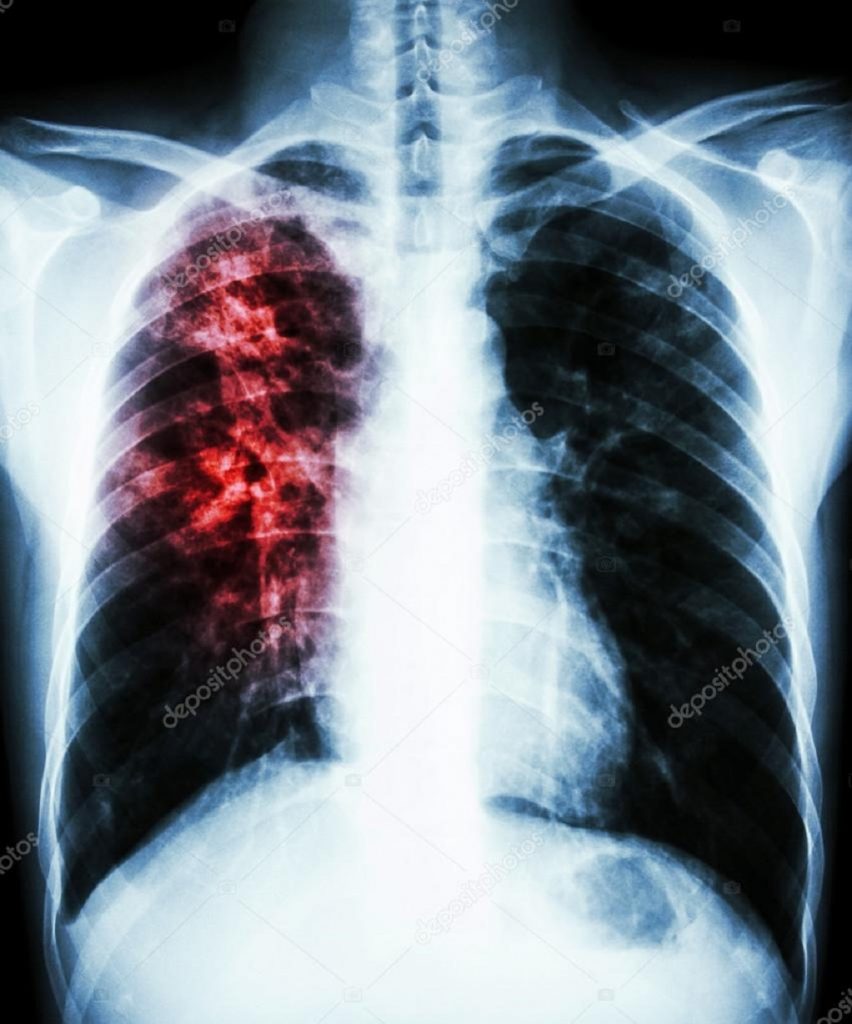

एक वर्षमा चार सय बढी नयाँ क्षयरोगी

कञ्चनपुर । सुदूरपश्चिम प्रदेशका पाँच जिल्लामा एक वर्षको अवधिमा ४३१ नयाँ क्षयरोगका बिरामी फेला परेका छन् । आर्थिक वर्ष २०७६/७७ मा कैलाली, कञ्चनपुर, डडेल्धुरा, डोटी र अछाम जिल्लामा गरिएको सम्पर्क परीक्षणबाट नयाँ क्षयरोगका बिरामी फेला परेका हुन् ।